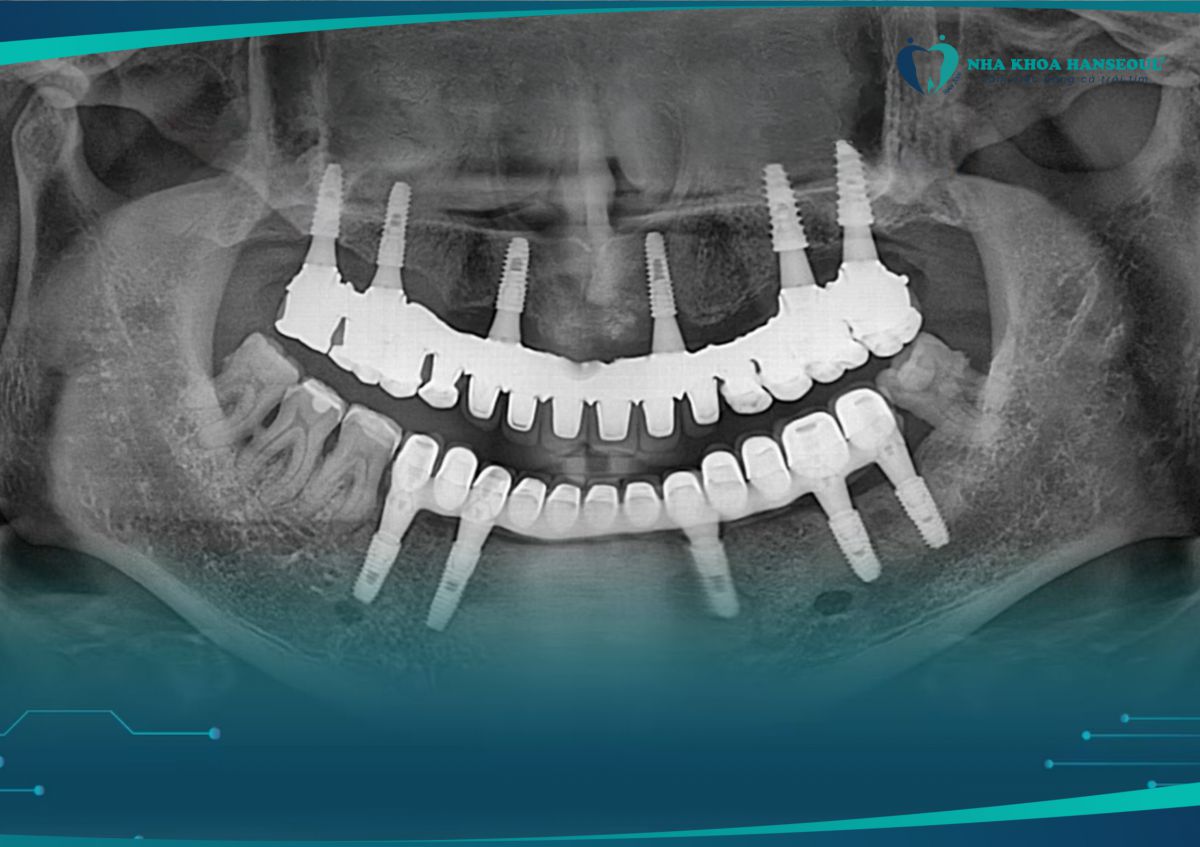

Kết quả chụp phim kiểm tra sau 8 năm cấy toàn hàm trên

Sau gần 10 năm, kết quả vượt ngoài mong đợi: “xương không tiêu, không viêm nhiễm, chức năng nhai chắc khỏe như răng thật”. Nhờ công nghệ Hansafe độc quyền, mỗi ca cấy ghép implant tại Hanseoul đều đảm bảo an toàn, chính xác và hiệu quả lâu dài.

Trồng implant 2 hàm tại Hanseoul, đến nay đã gần 10 năm mà vẫn bền đẹp – khỏe khoắn